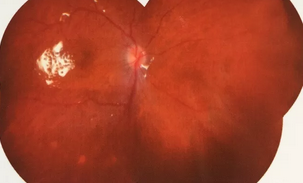

独眼,视网膜全脱离已成窄漏斗状、陈旧性葡萄膜炎、瞳孔后黏连无法散大,且并发白内障使得视网膜周边部细节情况无法看清,左眼已无光感,角膜白斑,瞳孔闭锁,还填充着硅油。右眼既往葡萄膜炎病因不清,一年中发病3、4 次都是用激素医治。左眼多年前是“天那水”溅入后又发生玻璃体出血手术后……令人担心的是这次我们克服重重困难救治全部脱离的视网膜 后,可能会面对长期慢性葡萄膜炎、长期药物医治的继发性高眼压,以及葡萄膜炎的再次复发等,稍有不慎就是不逆性致盲了。

手术室外,是家属们焦灼的等待。手术室内,是赵院长肩负重任带领大家紧张抢救。这是一场与时间赛跑、与病情赛跑,从黑暗到光明的抢救医治。赵铁英院长全神贯注、时而需要屏住呼吸如履薄冰般地操作、目不转睛同时双脚控制显微镜和机器参数,双手紧密配合,在如同混浊的海底世界的眼球腔内修复重建……

后,终于新旧病变处理完毕,展平复位了即将全部粘连在一起的视网膜,手术获得了 !没有下夜班仍继续在医院组织会诊参加手术的助手龙飘飘医生也长舒了一口气说:挽救了一个眼,挽救了一个人,挽救了一个家庭!